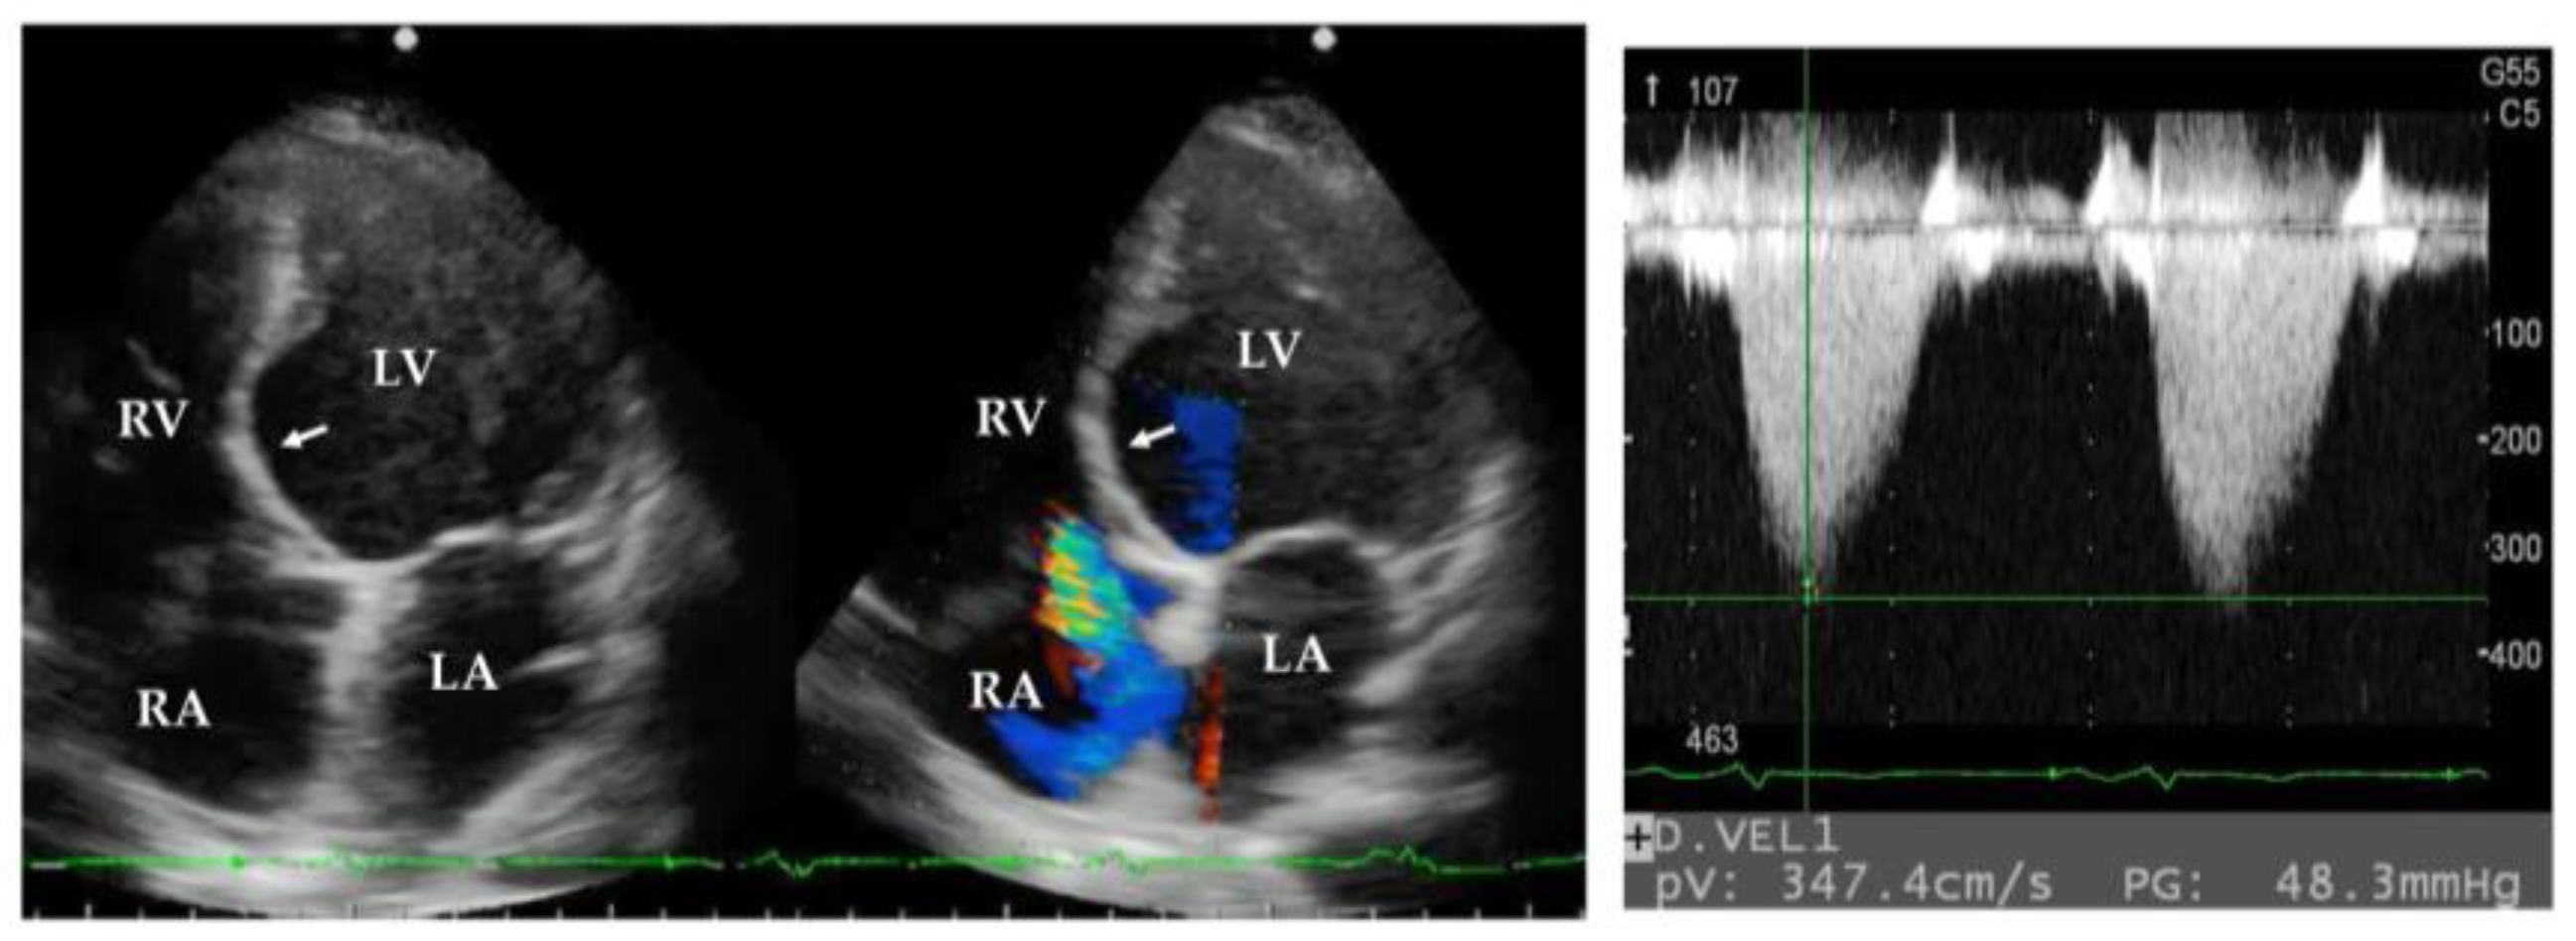

5.4. Echocardiography and Cardiac Catheter